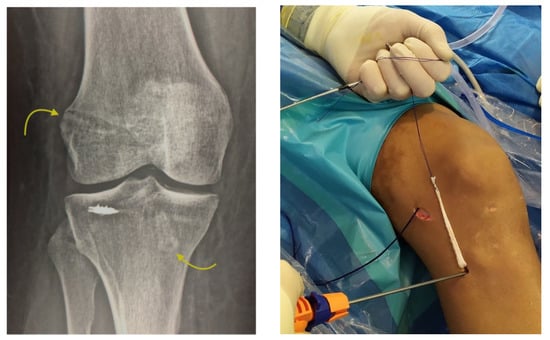

Approximately 97% of extra-capsular repair cases with LET combined with ACL reconstruction relied on implants placed on the lateral tibial surface at a location point situated halfway between the fibular head and the Gerdy´s tubercle by means of a minimally invasive incision (Figure 4).

Figure 4. Anterolateral fixation of the plasty at the time of lateral extra-articular (LET) (see footprint selection on the text). Arrows show femur and tibia tunnels with two interence screws fixation across out-in technique. Minimally invasive surgery for introducing the TWINFIX into the bone is showed.